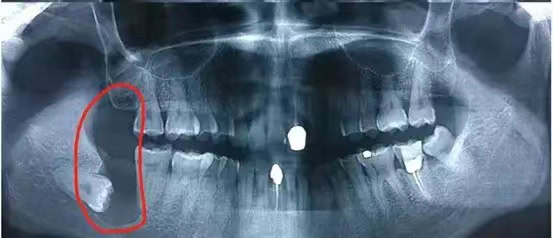

基於上述原因,當智齒的萌發對口腔健康構成威脅時,牙科醫生可能會建議進行拔除手術。拔牙前,醫生會進行全面評估,包括X光檢查,以確定智齒的位置和狀態,並根據具體情況決定最適合的治療方案。智齒拔除是一種常見的手術,技術成熟,風險相對較低,但術後仍需注意口腔衛生,遵循醫生的護理指導,以促進愈合並避免感染

- X光片是評估智齒狀態的重要工具。通過X光片,牙醫師可以了解智齒的實際位置、方向、鄰近牙齒與顎骨的關係,以及是否存在潛在的問題如牙根吸收、囊腫或腫瘤等。

根據阻生智齒的位置和方向,拔除的難度和風險也會有所不同。垂直阻生相對較易處理,而近中阻生或遠中阻生可能需要更複雜的手術程序。阻生智齒的確切類型往往需要通過X光片或CBCT(錐形束計算機斷層攝影)等影像學檢查來確定,以便醫生能正確評估情況並規劃適當的治療方案。